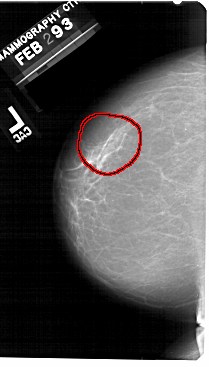

A_1493_1.LEFT_MLO

LEFT_MLO LINES 5416 PIXELS_PER_LINE 3301 BITS_PER_PIXEL 12 RESOLUTION 43.5 OVERLAY

FILE: A_1493_1.LEFT_MLO.OVERLAY

TOTAL_ABNORMALITIES 1

ABNORMALITY 1

LESION_TYPE CALCIFICATION TYPE PLEOMORPHIC DISTRIBUTION SEGMENTAL

ASSESSMENT 4

SUBTLETY 4

PATHOLOGY BENIGN

TOTAL_OUTLINES 1

BOUNDARY